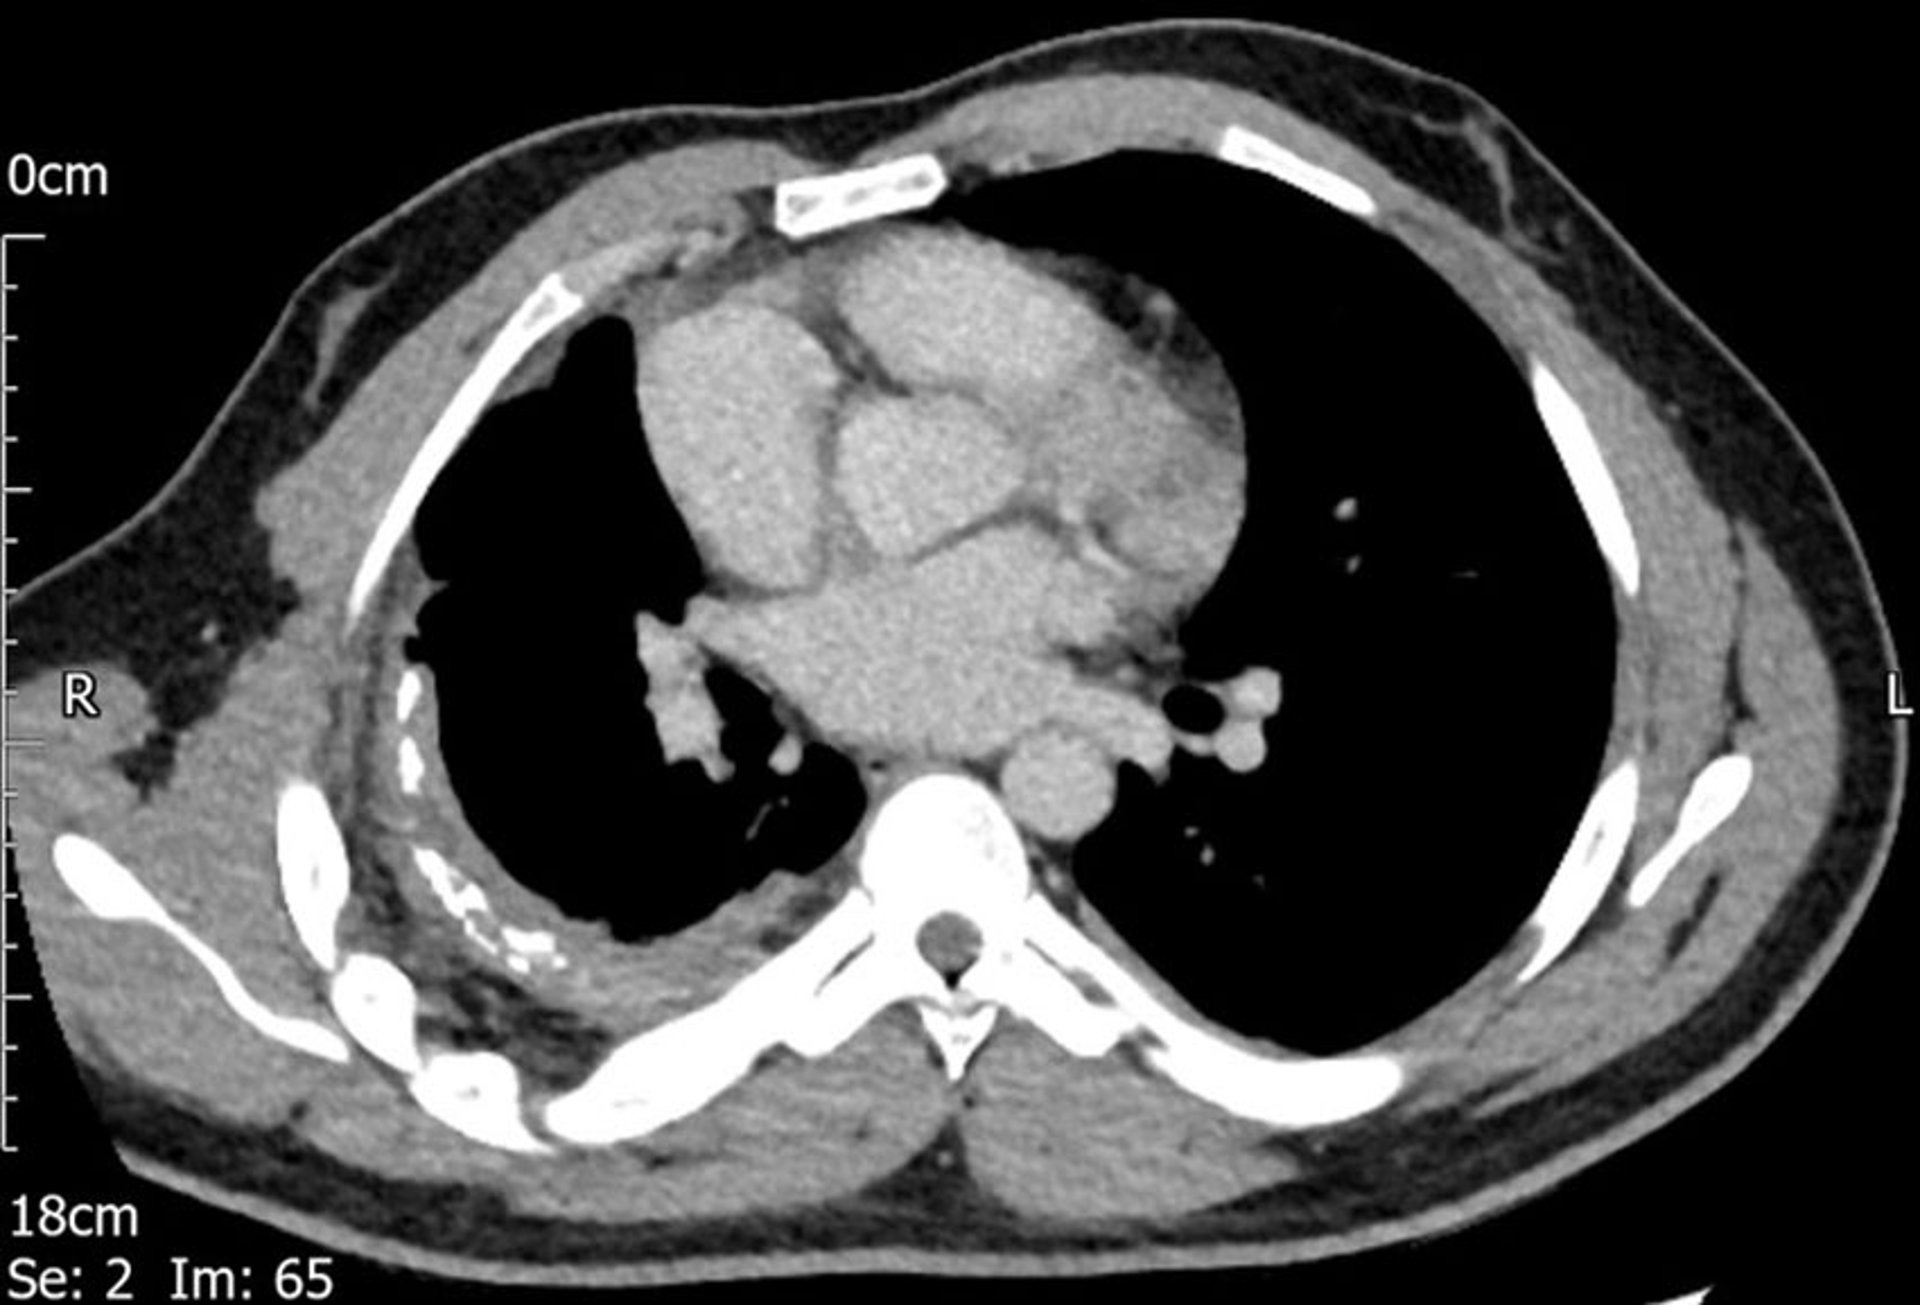

Un épaississement pleural est visible à droite sur cette TDM.

Image courtoisie de Najib M. Rahman, BMBCh MA (oxon) DPhil.